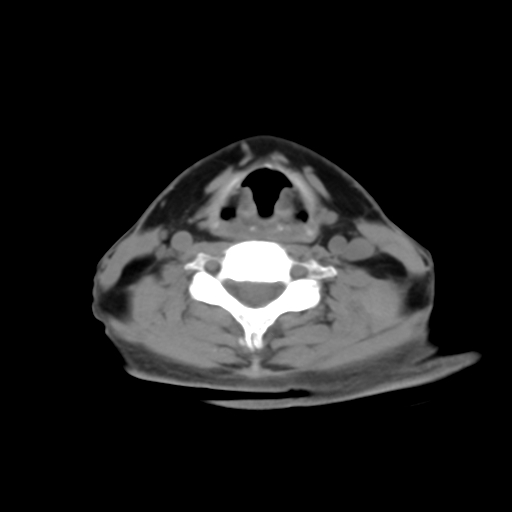

标题: CT24019:男,45岁,发现颈部肿物5个月。 [打印本页]

标题: CT24019:男,45岁,发现颈部肿物5个月。

男,45岁,发现颈部肿物5个月,彩超示:双侧颈部及下颌部软组织增厚。

考虑双侧颈项部良性对称性脂肪增多症。